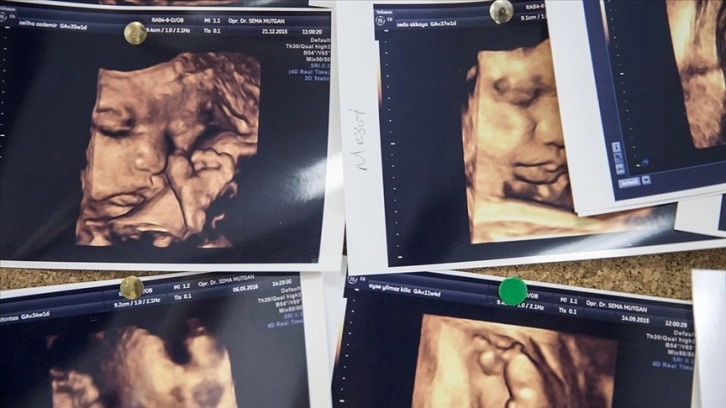

Anne karnındaki bebek sayısının iki veya daha fazla olması durumuna çoğul gebelik deniliyor.

Kovid-19 salgını sırasında, halk arasında "tüp bebek" olarak da bilinen IVF (in-vitro fertilizasyon) ve IVF benzeri üreme tedavilerinde aksaklıklar yaşandı. Aynı zamanda, Kovid-19 kısıtlamaları da sosyal hayatın yanı sıra ekonomik etkinlikleri de sekteye uğrattı.

Salgın sonrasında, tedavilerdeki aksaklıkların giderilmesi ve kısıtlamaların kaldırılmasıyla ABD, Fransa, Güney Kore, Çin ve Türkiye'de çoğul gebelikte artış gözlemlenirken İngiltere'de azaldı.

Araştırmacılar oranlardaki değişimin, salgın sırasında tüp bebek uygulaması benzeri üreme tedavilerinde yaşanan aksamalardan kaynaklandığını düşünüyor.